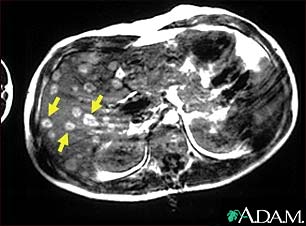

Melanoma of the liver - MRI scan

This upper abdominal MRI scan shows multiple tumors in the liver which have spread (metastasized) from a malignant melanoma in an arm or leg. Note the light circular areas throughout the liver (seen mostly on the left side of the screen).